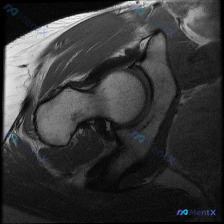

单一髋部MRI切面,能否诊断盂唇病变?

看到一份单一髋部MRI-T1序列冠状位图像的分析资料,重点讨论了盂唇病变的诊断问题。资料显示图像层面未见明确异常,但单一序列评估存在局限性,需结合多序列和临床检查判断。大家对此有什么看法?

首先放一下影像分析要点:

- 骨性结构:股骨头、股骨颈、髋臼等骨性结构连续、光滑,未见骨质中断或塌陷。

- 骨髓信号:T1WI上表现为中高信号,均匀一致,未见异常低信号灶。

- 关节间隙:双侧髋关节间隙清晰、等宽,关节面平整。

- 周围软组织:髋关节周围肌群形态完整,未见萎缩或异常信号。

- 盂唇病变:图像层面未见明确的盂唇撕裂、囊肿或异常信号。

但分析也提到,盂唇病变的诊断高度依赖多序列和多平面的MRI评估,单一T1序列冠状位图像敏感性有限。大家认为,针对髋痛患者,除了MRI,还需要结合哪些检查?